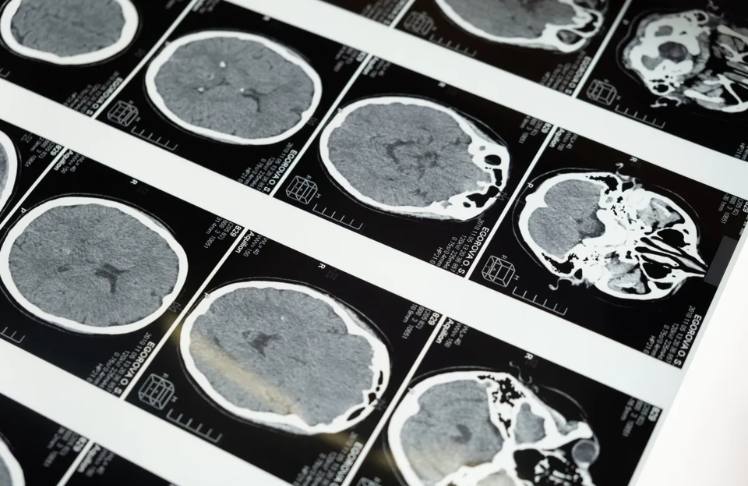

The researchers analyzed surveys and MRI brain scans of 7,350 white children and nearly 1,800 Black children, ages 9 and 10. They found that the Black kids were more likely to show changes in their brains linked to conditions like post-traumatic stress disorder (PTSD).

Specifically, in this study, the researchers found that Black children had less gray matter — brain tissue that processes information — in three essential areas.

The areas are the amygdala, which determines how people respond in a crisis; the hippocampus, responsible for learning and memory; and the prefrontal cortex, where reasoning, planning, judgment, and impulse control take place.